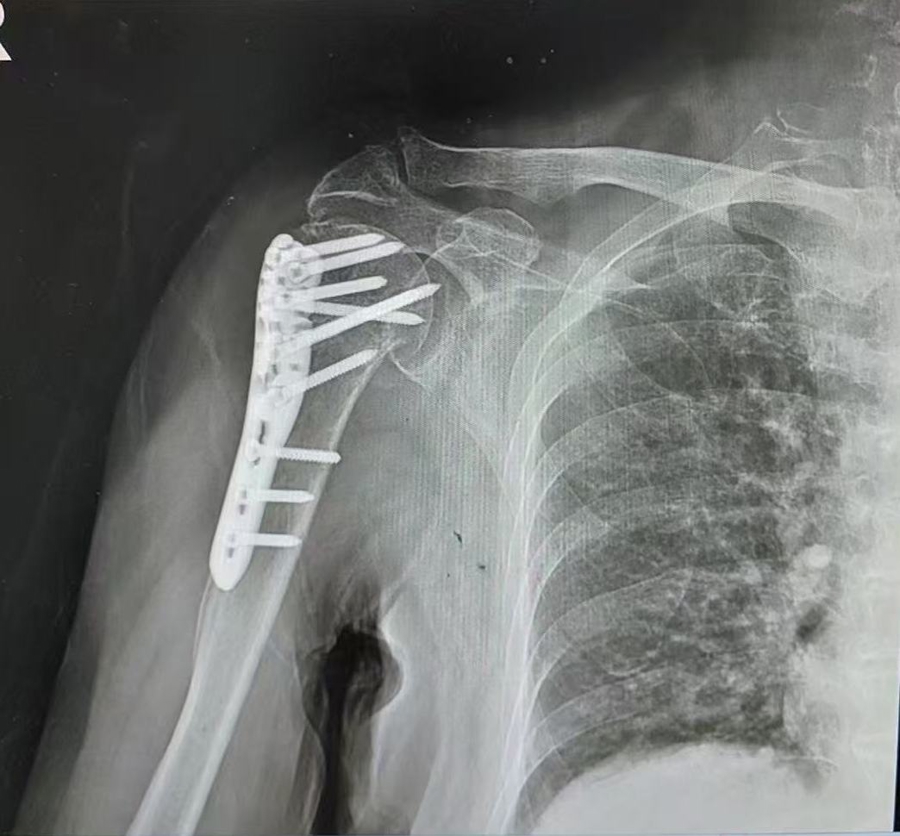

眼见老伴颠仆后失去强劲,孙老伯一时乱了方寸,赶快向前搀扶、连声招呼。一旁的存眷路东谈看法状,主动襄理拨打了120急救电话。大要脱落钟后,救护车抵达现场,将高阿婆送往就近的第十东谈主民病院救治。经CT查抄会诊,高阿婆右侧踝要津、右侧肩要津等共三处骨折,伤情较为严重,需立即剿袭调治。

CT自大多处骨折